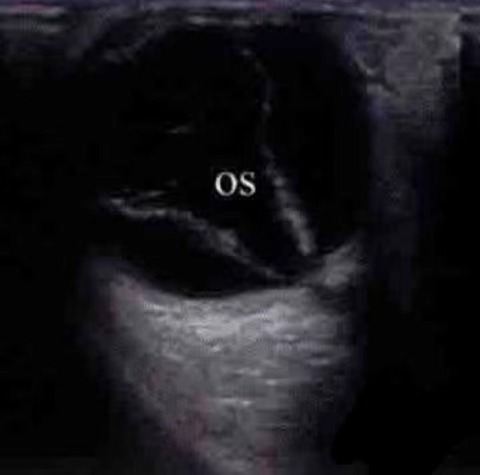

6、眼B超:如果患者已經(jīng)出現(xiàn)玻璃體出血,眼底無法看清,需要通過B超檢查看看視網(wǎng)膜是不是在位。